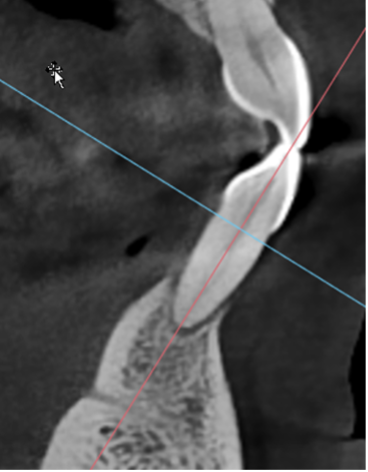

The Proof Is in the Bone

Look at tooth #24. Bone regenerated.

This wasn’t magic. It was the result of:

-

- Removing traumatic occlusion

- Identifying the bacterial profile

- Using appropriate antibiotics

- Thorough root debridement under direct visualization